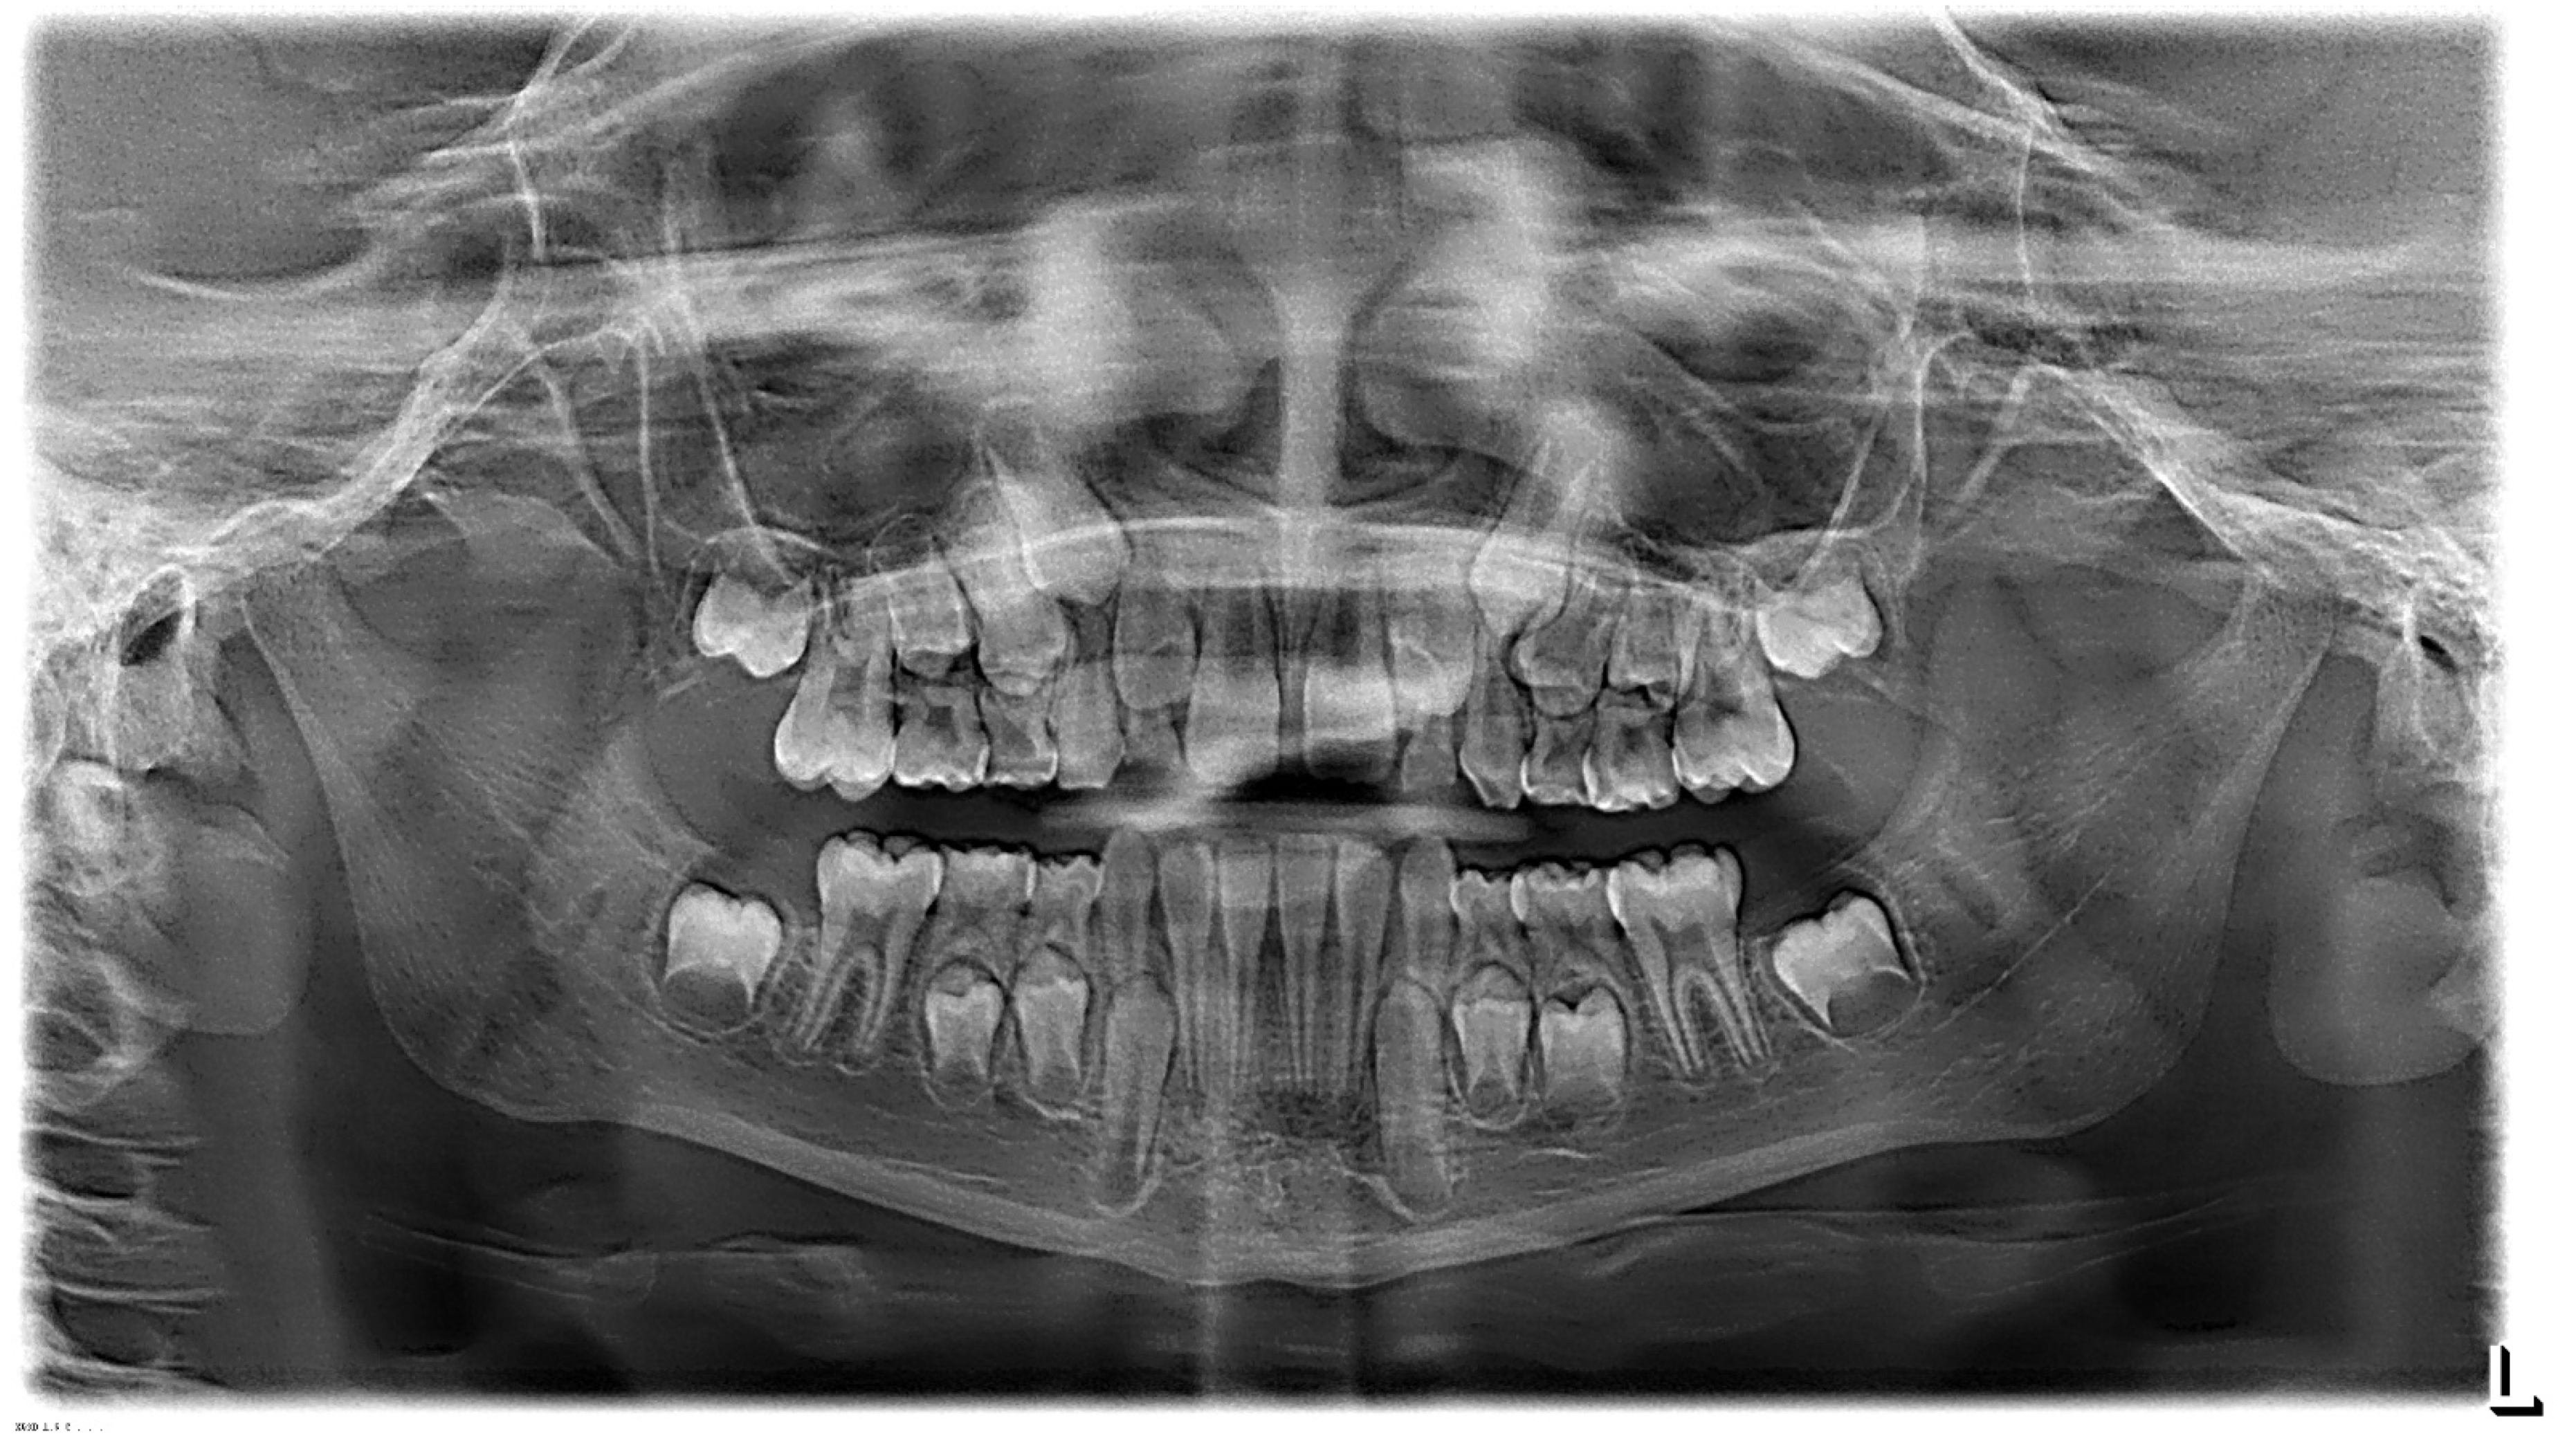

3.1. Clinical Case #1

3.2. Clinical Case #2

3.3. Clinical Case #3

3.4. Clinical Case #4